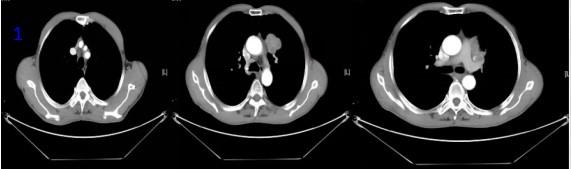

男性,61歲 ,因“確診左肺癌4月余,痰中帶血3天”入院?;颊哂?020年6月30日因"咳嗽、咳痰"在家人陪同下前往滕州某醫(yī)院行健康查體,行胸部CT提示左肺上葉占位性病變,左肺門及縱隔4R區(qū)可見腫大淋巴結(jié)(圖1)。2020年7月3日行CT引導(dǎo)下肺穿刺活檢,病理檢查示:(左肺穿刺活檢)分化差的癌,結(jié)合免疫組化結(jié)果考慮鱗狀細(xì)胞癌。免疫組化示:CK廣(+) CK5/6(+), P40(+),TF-1(-),CX7(-),CD56(-), NapsinA(-),CgA(-),Syn(-),Ki67(約50%陽性)。2020年7月-10月在外院完成“(白蛋白型)紫杉醇300mg,d1+洛鉑50mg,d1”化療3個周期,2020年10月20日復(fù)查胸部CT,腫瘤較前縮小,療效評價PR(圖2),患者因IV度骨髓抑制,嚴(yán)重乏力、納差未在繼續(xù)化療。近3日患者出現(xiàn)咳嗽,痰中帶血3天,病人為求進(jìn)一步治療到我院就診,門診以“左肺癌”收入院?;颊呶鼰?0年,20支/日,偶爾飲酒。既往史、婚育史、家族史無特殊。

圖1胸部CT:左肺腫瘤及腫大淋巴結(jié)

圖2 胸部CT可見腫瘤經(jīng)化療后減小